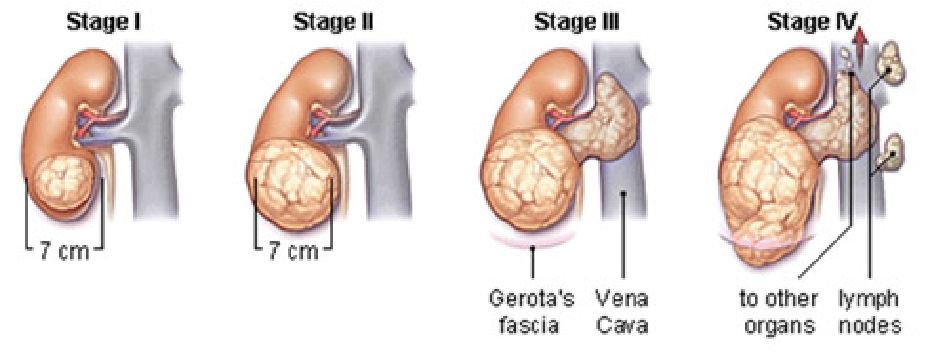

Οι θεραπείες που εφαρμόζονται για την θεραπεία του καρκίνου του νεφρού, εξαρτώνται κυρίως από το στάδιο της νόσου, το μέγεθος του όγκου, την ηλικία αλλά και την γενικότερη κατάσταση που βρίσκεται ο ασθενής.

Εικ. 2 : Τα 4 στάδια του καρκίνου του νεφρού

Θεραπεία του εντοπισμένου καρκίνου του νεφρού (Στάδιο Ι-ΙΙ)

Εντοπισμένο ονομάζουμε τον καρκίνο που εξακολουθεί να περιορίζεται εντός των ανατομικών ορίων του νεφρού, χωρίς να έχει επεκταθεί σε άλλες ανατομικές δομές, όπως λεμφαδένες ή άλλα όργανα (Εικ. 3,4).

Θεραπεία του τοπικά προχωρημένου καρκίνου του νεφρού (Στάδια ΙΙΙ-ΙV)